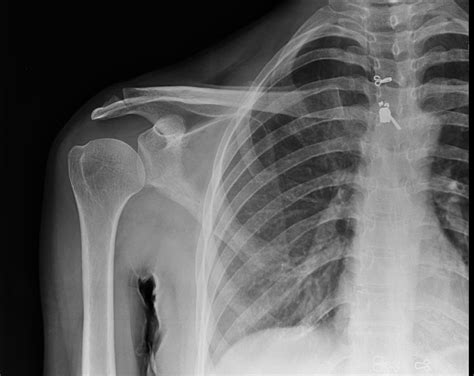

• AC Joint Separation: This occurs when the ligaments supporting the AC joint are torn, often due to a fall or direct impact. It is graded on a scale from I to VI, with higher grades indicating more severe injuries.

• Fractures: Breaks in the clavicle or scapula can be clearly seen on an X-ray. These fractures often result from high-impact injuries.

• Osteoarthritis: Degenerative changes in the AC joint can lead to pain and stiffness. X-rays can show bone spurs and narrowing of the joint space.